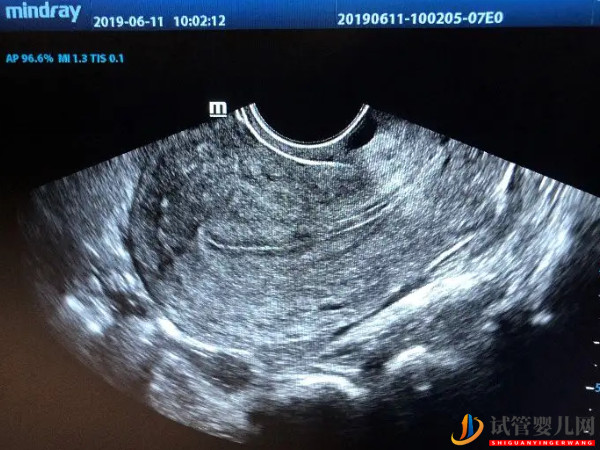

子宮內膜厚4.4mm狀態(tài)正常也別急!移植最佳厚度還沒到

內膜的厚度會跟隨者月經(jīng)周期而變化,主要分為增殖期、分泌期、月經(jīng)期,然后內膜會從薄變厚,如果內膜偏薄或過厚,那么都會影響到月經(jīng)的來潮以及懷孕,當發(fā)現(xiàn)內膜厚度不正常時,這時最好是進行治療。有很多人其實也問到,內膜厚度4.4mm是處于說明狀態(tài),這個厚度又能否移植胚胎?那么詳情的信息,在下文中就能了解。

子宮內膜厚4.4mm如果處于增殖期,是屬于一種正常的現(xiàn)象。內膜在月經(jīng)周期的第五天是最薄的,在月經(jīng)前潮前是最厚的,增殖期是月經(jīng)周期第5日到第14日,子宮內膜厚度從0.5毫米到5毫米,這時子宮內膜增殖的早期,內膜是最薄的。并且內膜在4.4mm也就是正常的,但如果正除去月經(jīng)期或分泌期,這個厚度顯然是偏薄的。

隨著月經(jīng)周期的結束,由于激素水平的作用,子宮內膜開始逐漸的增厚。在月經(jīng)前,也就是分泌期,子宮內膜可能會達到10-18mm,所以內膜的厚薄要隨著月經(jīng)周期變化而變化。如果是在月經(jīng)前內膜4.4mm,那就說明子宮內膜太薄。子宮內膜過薄可能會造成不孕癥,或者是月經(jīng)量過少,臨床就需要進行治療。

是不可以移植的,做試管嬰兒要移植胚胎的時候,子宮內膜的厚度需要達到7mm才行,通常內膜7-14mm屬于是可移植的范圍,8mm是最合適移植胚胎的厚度,如果內膜偏薄或偏厚都是不利于胚胎著床的,會影響到懷孕,基本是自然懷孕的,如果內膜4.4mm也是會影響到受精卵著床的。